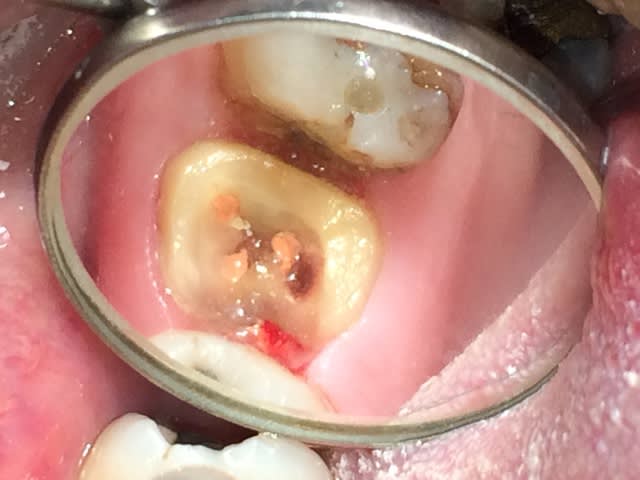

21/02/2014 à 01h05

Celui là m'a fait chier. je l'ai trouvé juste avant de prendre l'empreinte de mon ic-coiffe ( Têtu + plus de visibilité due à une cavité d'accès améliorée lol!) Spécial dédicace pour les pulpolithes qui ne m'ont pas facilité la tache.

L'orifice de ce petit enfoiré était juste à coté du canal palatin.